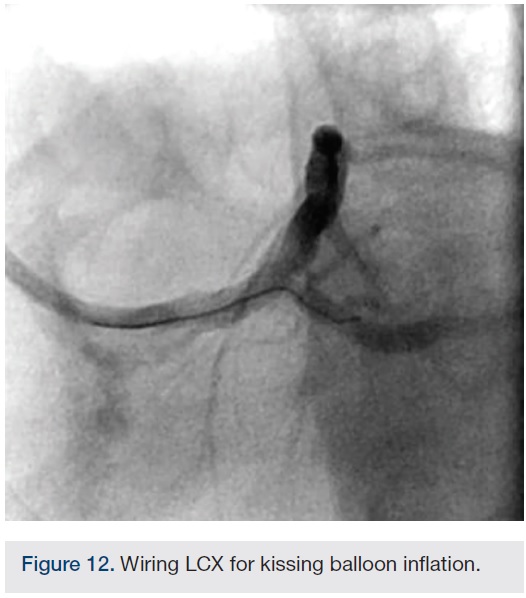

Following successful completion of the peripheral phase, it was felt that a 4-week period was necessary for the iliac stent to heal somewhat (especially since we planned to place a 14 French Cook sheath through it). We then moved on to the coronary phase of this procedure. Bilateral groins and the right wrist were prepared and draped in the usual sterile fashion. Using micropuncture technique with fluoroscopic verification of needle entry into the left CFA at the upper quadrant of the femoral head, a 6 French sheath was placed in the left CFA. The existing left femoral arterial sheath was removed, and the arteriotomy was pre-closed with a single Perclose device (Abbott Vascular). The arteriotomy was then serially dilated with 10, 12 and 14 French dilators, and a 14 French, 30 cm Cook sheath was placed successfully in the left common femoral artery. Following therapeutic anticoagulation with intravenous heparin, a regular J-wire and a 6 French pigtail catheter were used to cross the aortic valve, and the catheter was used to exchange the J wire for the 0.018-inch Platinum Plus wire (Boston Scientific). The Impella CP (3.5) percutaneous left ventricular assist device (LVAD) (Abiomed) was inserted into the left ventricle over the Platinum Plus wire (Figure 8). The Impella was then activated and good flows were verified. Right radial artery access was obtained and a PB 3.0 7.5 French sheathless guide system (Asahi Intecc) was used to engage the left main coronary artery. The LAD was wired uneventfully using a Runthrough wire (Terumo) via a 1.25 x 6 mm over-the-wire (OTW) Sprinter balloon (Medtronic). This was then exchanged for a Viper wire (CSI). Orbital atherectomy of the proximal LAD lesion was performed with excellent results (80,000 rpm x 4 passes, 120,000 rpm x 2 passes) (Figure 9). The LAD wire was then exchanged for a Runthrough wire and the left circumflex (LCX) was wired with a BMW wire. Following plaque modification with orbital atherectomy, predilation of LAD was performed with 3.0 x 20 mm Chocolate Balloon (QT Vascular Ltd) (15 atmospheres x 60 seconds and 15 atmospheres x 30 seconds) (Figure 10) with an excellent result and no dissection (Figure 11). A 3.5 x 38 mm Promus stent (Boston Scientific) (14 atmospheres x 30 seconds) was placed from the left main into the proximal LAD lesion ensuring adequate coverage. The jailed LCX wire was recovered and re-placed in the LCX through the struts of the newly placed LM-LAD stent (Figure 12). Predilation of the LCX ostium was performed with a 2.5 x 8 mm Glider balloon (QT Vascular Ltd) (14 atmospheres x 25 seconds). The mid LAD was stented (ensuring overlap with proximal stent) with 3.0 x 16 mm Promus stent (16 atmospheres x 25 seconds). A final kissing balloon inflation of the LAD/LCX with an NC Sprinter 2.5 x15 mm balloon (Medtronic) into the LCX and a NC Sprinter 3.5 x12 mm balloon into the LAD was performed, with up to 16 atmospheres x 20 seconds on both (Figure 13). Final IVUS of the LM and LAD stent revealed excellent results and the LCX ostium looked excellent as well (Figures 14-16).